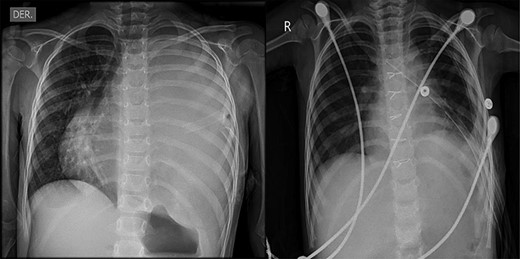

Anatomical pathology test showing the presence of glandular epithelial cells (yellow arrow) concomitant with the presence of cartilage tissue (green arrow)

The patient underwent a total resection of the mediastinal mass via a median sternotomy. Given the extension of the teratoma and adhesions to the chest wall, an additional approach with a left anterior thoracotomy was made (Fig. 2). Entry into the pleural space was performed through the sixth intercostal space to obtain safe visualization of the cavity and proceed to tumor excision. Many adhesions were found to the thoracic wall, diaphragm and phrenic nerve. Additionally, a nutritional artery depending on left internal mammary artery was discovered with collateral veins draining to brachiocephalic vein. A section of the left internal mammary vessels, dissection of the phrenic nerve, ligation of the nutritional vessel, mediastinal tumor excision, ligation of the thymic vessels and thymectomy was performed. Thoracic drainage tubes (two) were placed. The mediastinal tumor, excised in block, was red–gray colored, well circumscribed and capsuled with a size of 15 × 15 × 20 cm. Postoperatively, the collapsed left lung was re-expanded, and the patient was extubated on Day 1 (Fig. 3). The patient recovered from the operation and was discharged on the ninth postoperative day. Preoperative atelectasis of the left lung partially resolved, and the pathological examination revealed a benign mature teratoma with cystic degeneration. Anatomical pathology test showed the presence of glandular epithelial cells concomitant with the presence of cartilage tissue (Fig. 4) The histochemistry test revealed CD3(+) CD20(+) TDT(−) CD5(−) cells. Thymic tissue was negative for malignancy; nine lymph nodes showed reactive follicular hyperplasia.